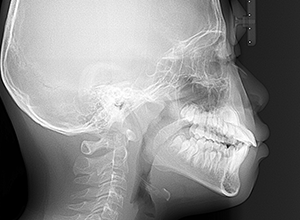

| X-Ray所見 | |

| セファロ所見 | Sellaに対して下顎頭は後方位だが下顎骨は大きくしっかりとした形態をしており前後的にはⅠ級、垂直的にはロウアングルの骨格形態をしていた。 上顎前歯は唇側傾斜を呈していた。 |